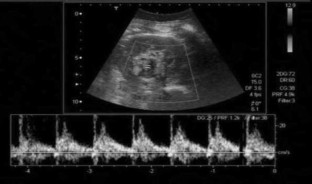

A 40-year-old woman was referred to our department for further investigation of a renal mass identified at an ultrasound (US) examination carried out in a private clinic because of abdominal pain. The mass was oval and hypoechoic, measured about 20 mm in diameter and was located near the left renal sinus; color Doppler showed peripheral blood flow. US examination carried out in our department using different equipment confirmed the presence of the mass but revealed intralesional blood flow suggesting aneurysm. This diagnosis was confirmed at subsequent computed tomography (CT) scanning and magnetic resonance imaging (MRI). The patient refused to undergo surgery and she is currently being monitored and has suffered no sequelae.

Fig. 3